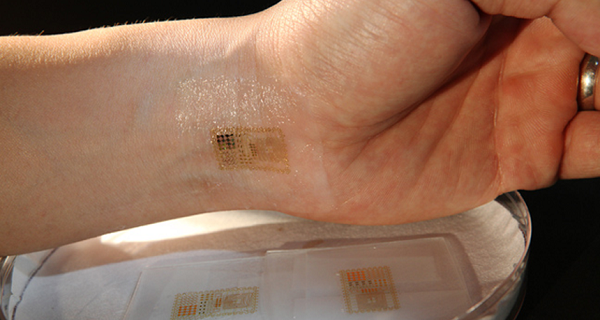

راجرز و همکارانش دستگاهی الکترونیکی ساختهاند که کوچکتر از یک تمبر پستی بوده و مانند یک خالکوبی موقت به پوست میچسبد. کاربران احتمالی این وسیله بیماران، ورزشکاران، پزشکان، مأموران مخفی و حتی شما را میتواند شامل شود.

این وسیله با قرار گرفتن بر روی پیشانی میتواند امواج مغزی و بر روی مچ دست، جریان خون و حرکات عضلانی را ضبط کند.این وسیله با قرار گرفتن بر روی پیشانی میتواند امواج مغزی و بر روی مچ دست، جریان خون و حرکات عضلانی را ضبط کند. با قرار دادن این وسیله بر روی پوست بیماران میتوان علائم حیاتی آنها را ردیابی کرده و مشکلات آنها را تحت نظر بگیریم. این قطعه الکترونیکی همچنین میتواند جایگزین تجهیزات بزرگ بیمارستانها شود. و با قرار گرفتن بر روی گلو میتواند همانند یک تلفن همراه مخفی عمل کند به گونهای که با حرکت و جنبش حنجره فرد، دستگاه فعال میشود.

دانشمندان این وسیله را به اندازه حدود نصف ضخامت یک کاغذ معمولی و شبیه به پوست طراحی کردهاند. این ماده الکترونیکی را مانند پوست میتوان در بسیاری جهات کشید و به آن فشار وارد آورد، اما همچنان قادر است به کار خود ادامه دهد.

قطعهای الکترونیکی با قابلیت چسبندگی به پوست بدن انسان که میتواند خواص پوست را تقلید کند، بدین معنا که قادر است در مقابل ضربه، کشیدگی و فشردگی مقاومت نماید.

تود کولمن که دارای مدرک مهندسی است آزمایشهای سختی را پشت سرگذاشته و به دنبال یافتن راهی است که بوسیله آن بتواند میان این وسیله، بدن و ذهن ارتباط برقرار کند. او عنوان میکند: «یکی از این قطعات الکترونیکی را نزدیک ساعد خود قرار داده و مشت خود را گره کردم به این منظور که بتوانم نحوه نشان دادن حرکات و سیگنالهای عضلانی خود توسط این دستگاه را مشاهده کنم.» وی میافزاید: « اگر آن را بر روی سطح سر قرار دهید امواج مغزی را ضبط میکند. چنانچه نزدیک به قلب باشد، اطلاعات ضربان قلب را برمیدارد. دستگاه یکی است اما میتوان از آن در نواحی مختلف استفاده کرد».

به گفته کولمن این وسیله بسیار سبک بوده بطوریکه کاربر ممکن است وجود آن را فراموش کند. او اکنون در دانشگاه کالیفرنیا سن دیگو مشغول به کار است. او میگوید: «ما سعی داشتیم یک قطعه الکترونیکی طراحی کنیم که اساساً برای کاربر کاملاً نامرئی باشد. شما به سختی احساس میکنید که این وسیله بر روی بدنتان قرار دارد».